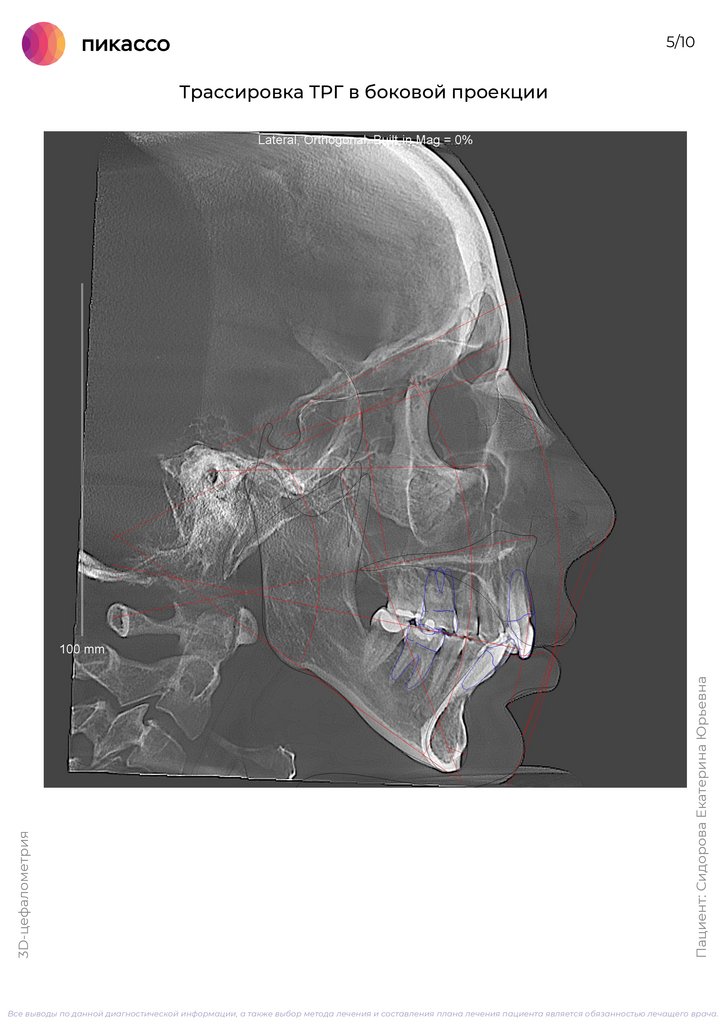

6.

5/10

Пациент: Сидорова Екатерина Юрьевна

3D-цефалометрия

Трассировка ТРГ в боковой проекции

Все выводы по данной диагностической информации, а также выбор метода лечения и составления плана лечения пациента является обязанностью лечащего врача.